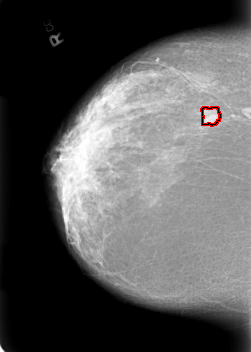

B_3020_1.LEFT_MLO

LEFT_MLO LINES 5672 PIXELS_PER_LINE 4160 BITS_PER_PIXEL 12 RESOLUTION 50 NON_OVERLAY

FILE: B_3020_1.RIGHT_MLO.OVERLAY

TOTAL_ABNORMALITIES 1

ABNORMALITY 1

LESION_TYPE MASS SHAPE LOBULATED MARGINS CIRCUMSCRIBED-ILL_DEFINED

ASSESSMENT 4

SUBTLETY 4

PATHOLOGY MALIGNANT

TOTAL_OUTLINES 1

BOUNDARY